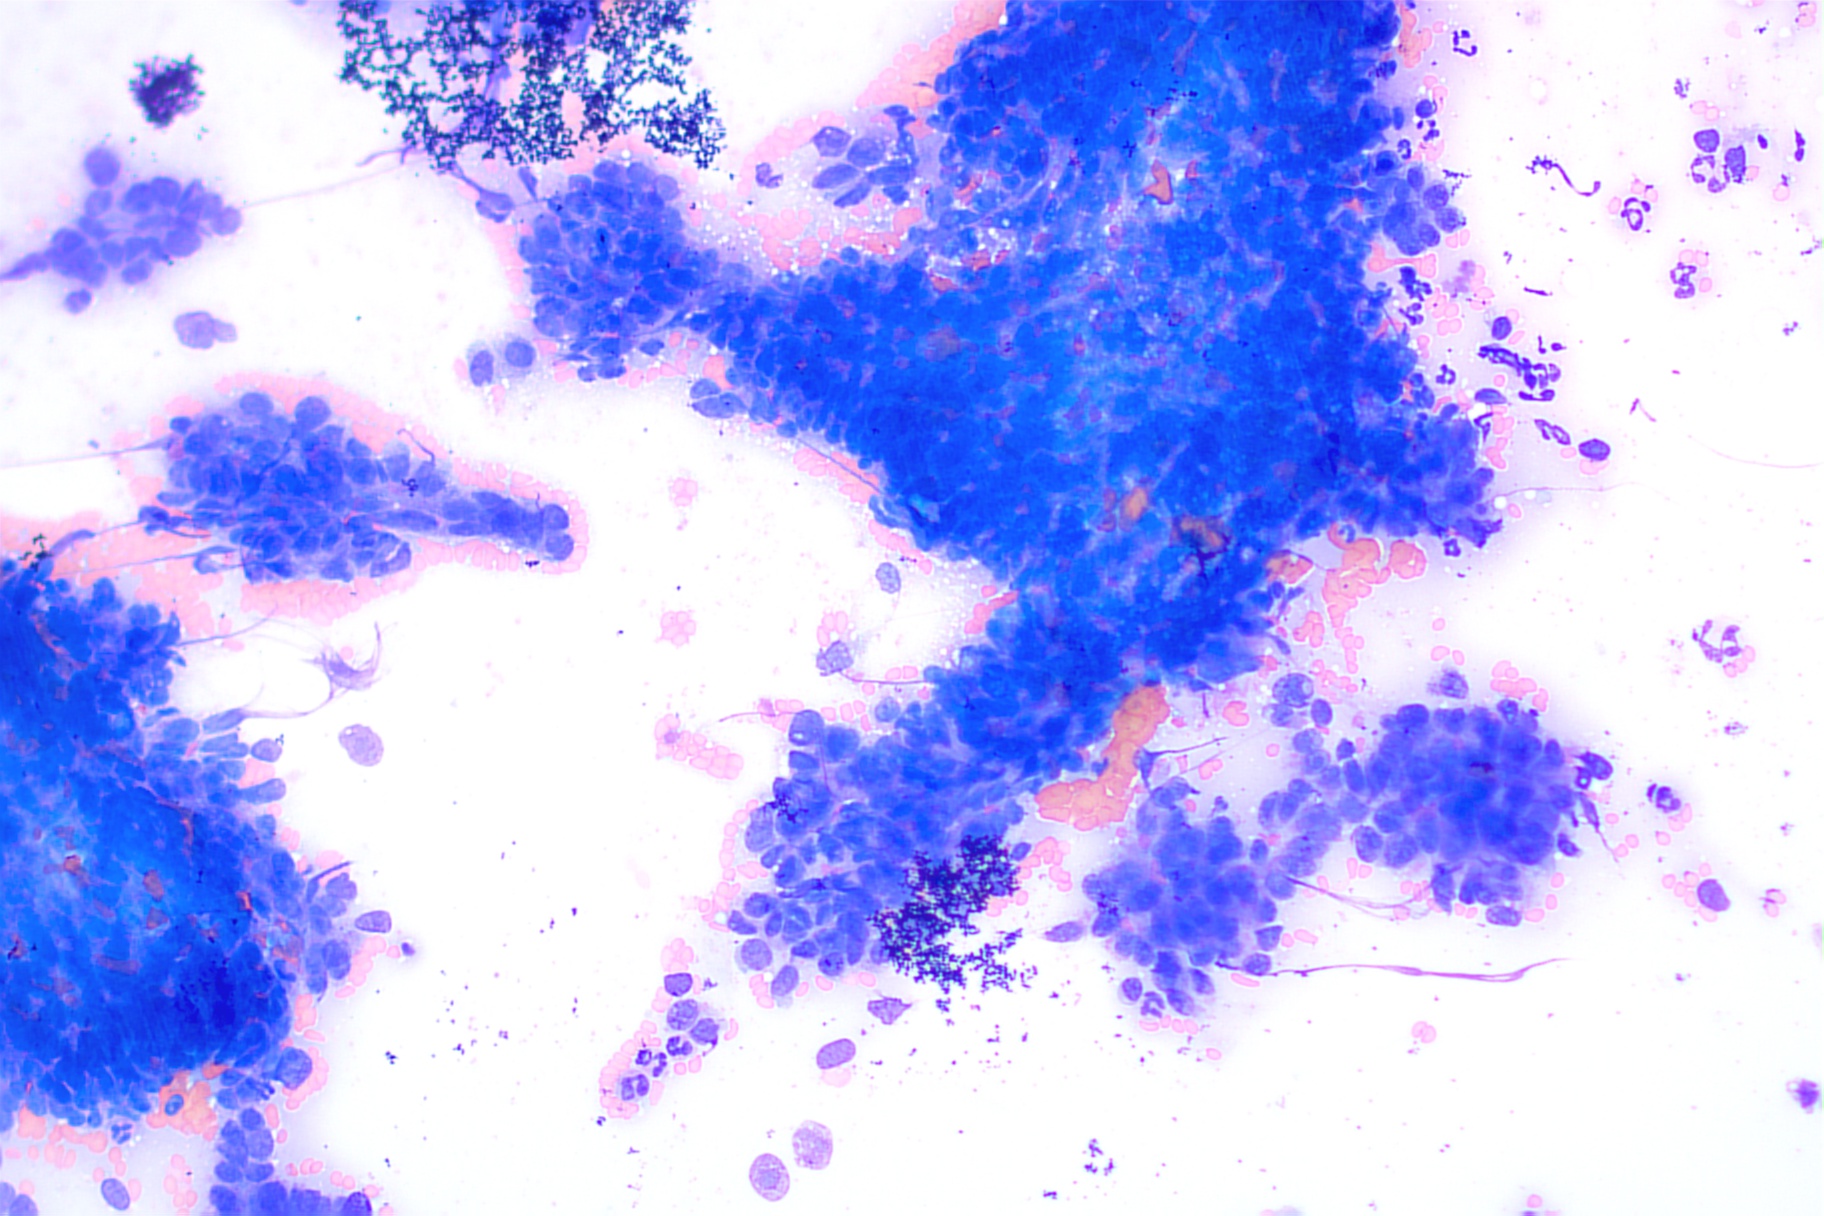

Image 4: Cytology

CYTOLOGIC DIAGNOSIS AND FINDINGS:

The cytologic findings are most consistent with a carcinoma at this site. Top considerations include biliary origin as well as hepatocellular origin. Biopsy with histopathology +/- immunohistochemistry would be recommended for further characterization as clinically warranted.

The sample is of focally moderate cellularity and adequate preservation. Cohesive clusters of neoplastic epithelial cells predominate in this sample with papillary-like formations, often associated with extracellular pink fibrillar material. These rounded to cuboidal cells have distinct cellular borders with a small amount of pale to medium basophilic cytoplasm. The round to oval nuclei measure approximately 1.5-3 times the diameter of erythrocyte with coarsely stippled chromatin, containing 1-2 small distinct nucleoli. Anisocytosis and anisokaryosis are moderate with a high nucleus to cytoplasm ratio. Neutrophils are rarely found on scanning, likely in accord with the degree of hemodilution. No infectious agents are identified.